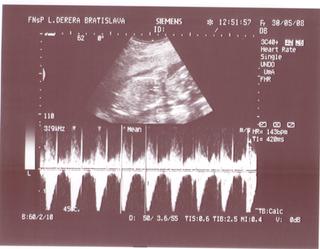

@lucy56 morfoligicky utz je zameraný na hodnotenie správnosti vývoja jednotlivých orgánov plodu a zároveň sa odmeraním určitých parametrov hodnotí aj správnosť rastu dieťaťa. nebudes tak dobre vidiet dietatko ako na 3D. 3D utz :Moderný 3D ultrazvuk umožňuje vidieť pohyby Vášho bábätka, ako na filmovom plátne. Pohľad do tváre pôsobí na budúcu mamičku ukľudňujúco. Prepočítajme spolu prstíky a presvedčme sa, že je všetko v poriadku.Celé vyšetrenie je možné uchovávať na DVD nosiči.Najvhodnejší je záznam v 22-26. týždni tehotenstva.